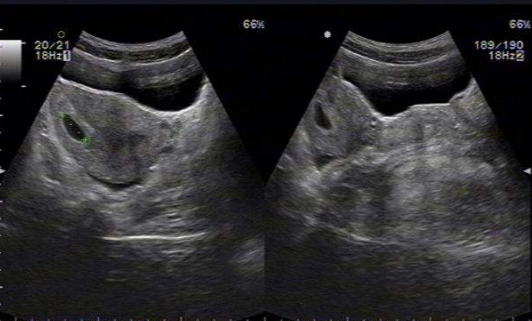

雙角子宮圖片

雙角子宮 (7)

雙角子宮 (8)

雙角子宮 (9)

雙角子宮 (55)

雙角子宮 (56)

雙角子宮 (57)

雙角子宮 (58)

雙角子宮 (59)

雙角子宮 (6)

雙角子宮 (60)

雙角子宮 (61)

雙角子宮 (48)

雙角子宮 (49)

雙角子宮 (5)

雙角子宮 (50)

雙角子宮 (51)

雙角子宮 (52)

雙角子宮 (53)

雙角子宮 (54)

雙角子宮 (44)